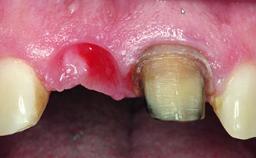

Replacement of a Compromised Upper Right Central Incisor: Hard- and Soft-tissue Augmentation, Late Placement of an RC Bone Level Implant

A 36-year-old male patient with a compromised maxillary central incisor was referred by his general dentist for consultation. The patient’s chief complaints were the gradual debonding of a temporary crown on the right central incisor and unsatisfactory esthetics due to an increasing diastema between the right central and lateral incisors. The patient reported a traumatic event some years previously, when a crown had been placed after root-canal treatment. The referring dentist wanted to provide a new crown restoration, but was concerned about the condition of the residual root. Anamnesis was negative for any other dental or periodontal pathology in the remaining dentition. The patient reported taking no medications: He was a smoker (10 to 15 cigs/day) and had realistic esthetic expectations.

Soft Tissue Anatomy Intact Defective

Bone Volume Horizontally and vertically sufficient Horizontally deficient Deficient vertically or deficient vertically AND horizontally

Soft Tissue Contour and Volume Slightly compromised